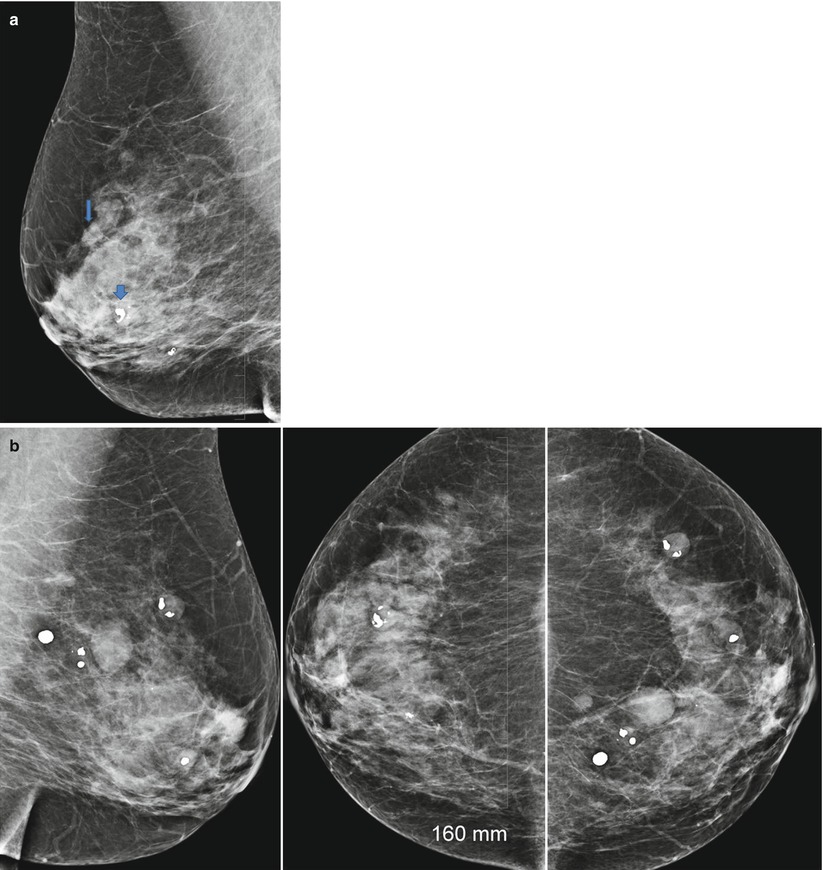

From link.springer.com

Interval growth of probably benign breast lesions on followup What Is A Probably Benign Finding This assessment means that the. That is, there is something abnormal on mammogram but it is not breast cancer or malignant in any. The findings are not expected to. Each number represents a specific finding, including incomplete, negative, benign, probably benign, suspicious,. This also a negative result, but to be complete it’s noted there are. What is the meaning of. What Is A Probably Benign Finding.